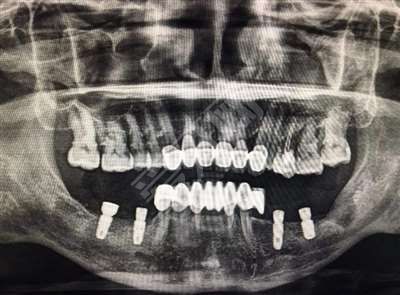

在Astra的基礎(chǔ)上,奧齒泰的植體結(jié)構(gòu)得到了改善,表面處理有SA和HA兩種,SA和SLA處理方法相似,也是噴砂+酸蝕,HA直接將顆粒噴在植體表面。

簡(jiǎn)而言之,高檔金屬通過(guò)精密計(jì)算機(jī)設(shè)計(jì)制成圓柱體,植入口腔內(nèi)的牙床骨。經(jīng)過(guò)3個(gè)月左右的恢復(fù),牙根與牙床骨緊密結(jié)合,然后在人工壓根上制作假牙。

1.植體表面采用多孔納米氧化鈦技術(shù)處理,植入后更容易存活。排斥小,成功率高。

2.對(duì)牙槽骨要求低,種植適應(yīng)癥廣,疏松性骨質(zhì)不再是禁區(qū)。

1.植體表面的多螺紋設(shè)計(jì)可以增加接觸面積,植入后穩(wěn)定性更高。

2.表面采用多孔納米氧化鈦處理技術(shù),排斥現(xiàn)象小,愈合速度加快,穩(wěn)定性進(jìn)一步提高。

3.底部獨(dú)特的設(shè)計(jì)使其具有更好的植入深度調(diào)節(jié)能力和更廣泛的適應(yīng)癥。